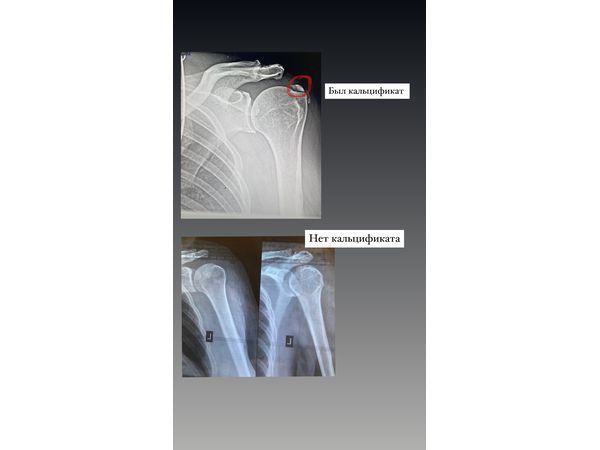

МРТ плечевого сустава показала:

- скопление солей кальция в сухожилии надостной мышцы размером 3×3 мм;

- воспаление длинной головки бицепса.

На снимках контрольной МРТ через 6 месяцев скопления солей кальция не было, сухожилие полностью восстановилось.